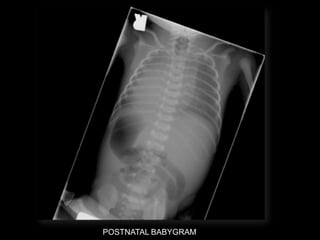

Dr. Ana Lourenco

HISTORY

• 36 yo female 30.5 weeks pregnant

• Referred with ‘multiple fetal anomalies’ for

fetal ultrasound

LUS – Cephalic

POSTNATAL BABYGRAM

• What are the findings?

• What is the diagnosis?